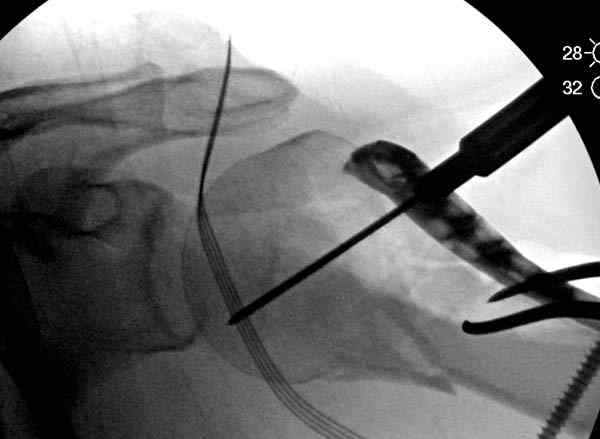

Здесь пример открытой репозиции 57 летнего с переломом плеча (1,2) смещение обнаружено на интероперационном снимке. При нормальной прямой проекция (3) угловое смещение обнаружили в аксиальной проекции (4)

После устранения смещения пластина установлена выше (5,6,7) и финальные снимки (8,9,10)